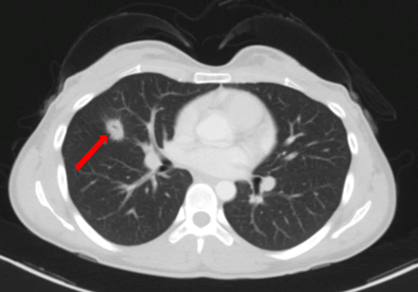

Bệnh nhân được chụp cộng hưởng từ sọ não, phát hiện khối u vùng đỉnh chẩm phải kích thước 39x46x43 mm, theo dõi tổn thương thứ phát

Hình 1. Hình ảnh cộng hưởng từ sọ não ngày 27 tháng 10 năm 2022 khối u não vùng đỉnh chẩm phải (mũi tên).